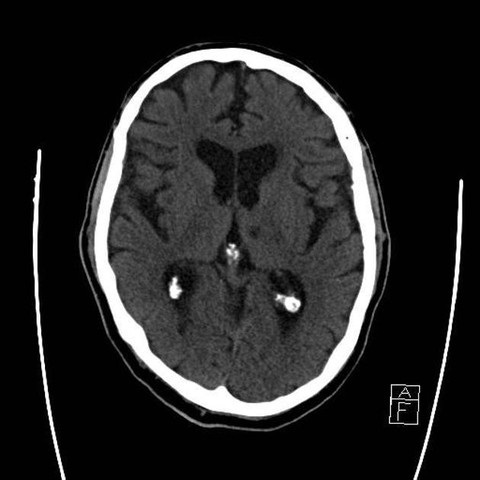

Tomografía

Paciente aporta tomografía de hace 5 meses.